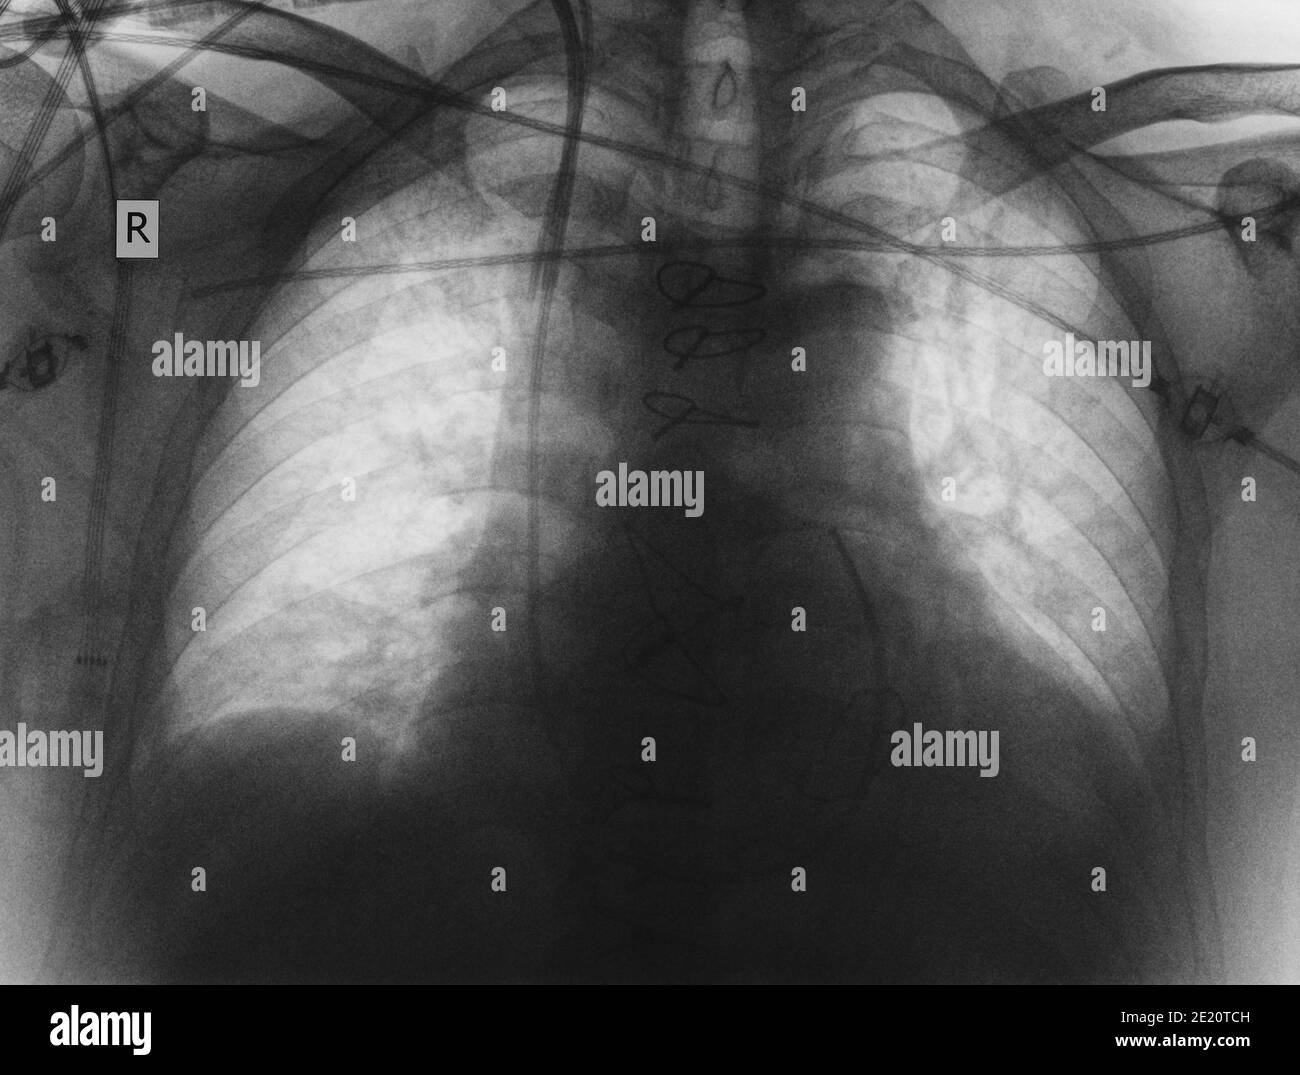

Chest Xray of patient 1, taken shortly after cardiac arrest and Open Heart Surgery Chest X Ray Sternum healing after open heart surgery can take months or years, depending on the person. If an enlarged heart occurs with chest pain or other signs of a heart attack, blood tests may be done to check the levels of. Men over the age of 50. Indicated only for patients with known pathology, congestive heart failure, or recent pneumonia. See. Open Heart Surgery Chest X Ray.

Chest Xray after cardiac resynchronization therapy with defibrillator Open Heart Surgery Chest X Ray Sternum healing after open heart surgery can take months or years, depending on the person. Indicated only for patients with known pathology, congestive heart failure, or recent pneumonia. See xrays of sternum before and after heart surgery including chest wires used after median sternotomy. Find out how to care for the wound and more. Men over the age of 50.. Open Heart Surgery Chest X Ray.

Postoperative chest X‐ray after open‐heart surgery in 2016 with aortic Open Heart Surgery Chest X Ray Open heart surgery is a serious medical procedure that may be necessary if you live with certain heart conditions, such as heart. Find out how to care for the wound and more. If an enlarged heart occurs with chest pain or other signs of a heart attack, blood tests may be done to check the levels of. Sternum healing after. Open Heart Surgery Chest X Ray.